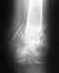

Добрый день! Три дня назад я упала, сегодня сделали снимки копчика в районной поликлинике, один врач думал перелом, другой подвывих.

Никаких проблем на снимке не видно. Либо это сильный ушиб, либо проблема в другом месте.